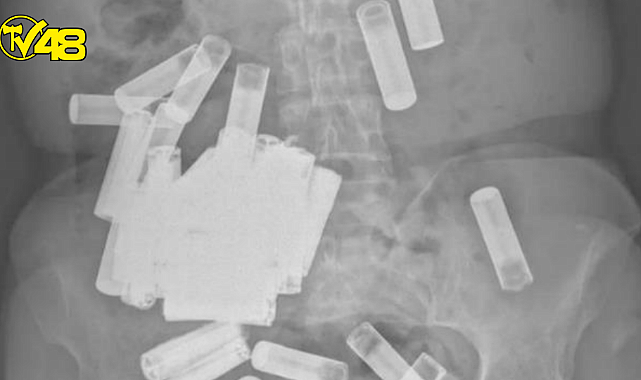

İÇİNDE 55 TANE PİL BULUNDU

Yaşlı kadının midesinde ve bağırsaklarında toplam 55 tane pil vardı. Doktorlar yaşlı kadın mide krampları yaşamaya başladığında, pillerin ağırlığı nedeniyle şişmiş midesinin kasık kemiğinin üzerine çıktığını keşfetti. Korkulan olmadı ve pillerin dışkılama yoluyla vücuttan çıkacağı ön görüldü.

4 PİLİ ÇIKARMAK ÇOK ZOR OLDU

İrlanda Tıp Dergisi'ndeki rapora göre, kadın ilk hafta içinde beş pili vücudundan atmayı başardı ancak geri kalanı sıkışmıştı. Bu sebeple cerrahlar harekete geçti ve kalan 46 pili çıkardılar. Ancak dördü hala bağırsağında sıkışıp kalmıştı. Bu sebeple doktorlar kalan pilleri rektumundan sağarak çıkardılar.